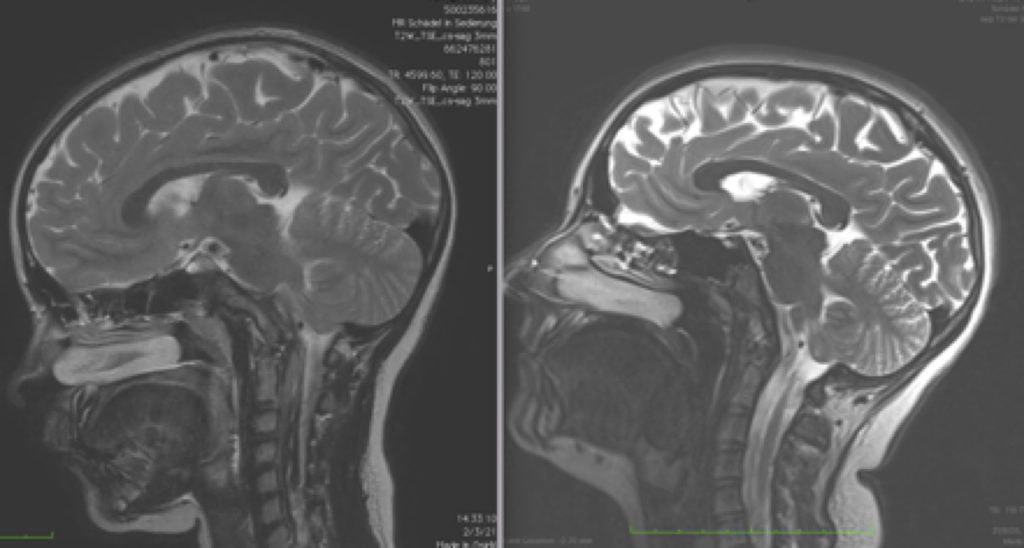

Le immagini di risonanza magnetica nel controllo postoperatorio dopo 4 anni dall’intervento, evidenziano che è stato raggiunto l’obiettivo del trattamento, bloccando l’avanzare della discesa delle tonsille cerebellari (Fig.1). Inoltre, la RX del rachide in toto mostra che la scoliosi si è corretta dopo l’operazione, con il raddrizzamento della curvatura della colonna vertebrale (Fig.2).

Fig.1 Postoperatorio del Caso 14236: Comparativa tra la RMN cranica preoperatoria del 2021 e quella di controllo del 2025 ai 4 anni postoperatori, che mostra invariata la discesa delle tonsille cerebellari